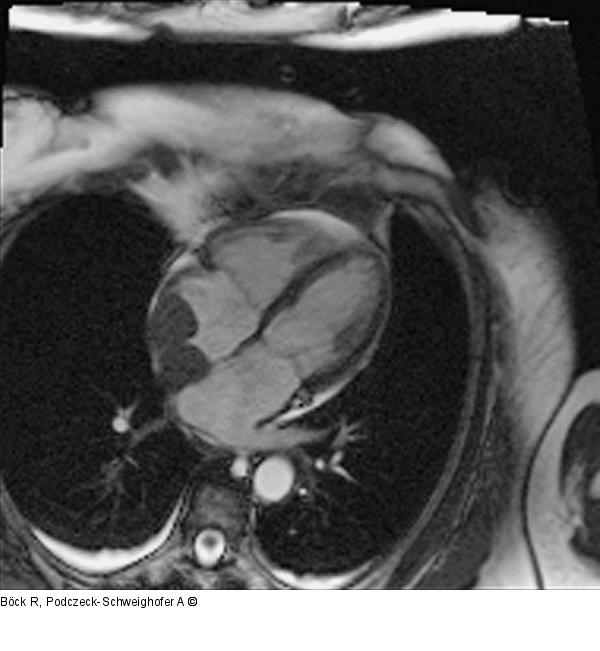

Abbildung 1: Kardiales NMR

Kardiales NMR